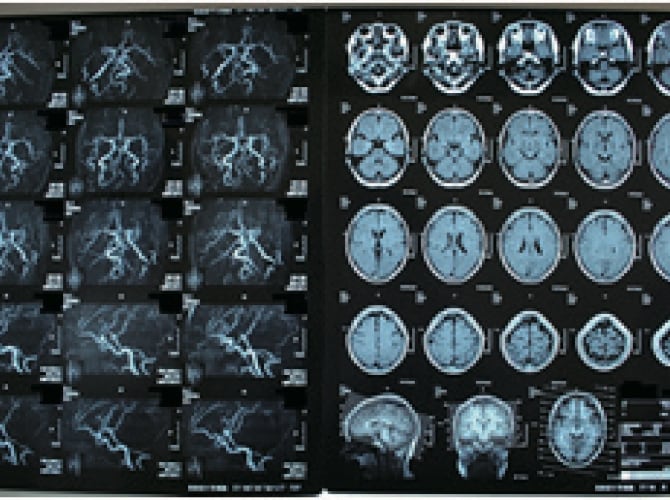

脳ドック

頭部MRI検査、頭頸部MRA検査、頸動脈超音波検査を行います。

脳梗塞、脳動脈瘤や脳腫瘍などの頭蓋内異常が発見されたり、動脈硬化や動脈狭窄などが明らかになります。

脳ドックを選択された場合、同時に認知症の簡易検査を受けることができます。